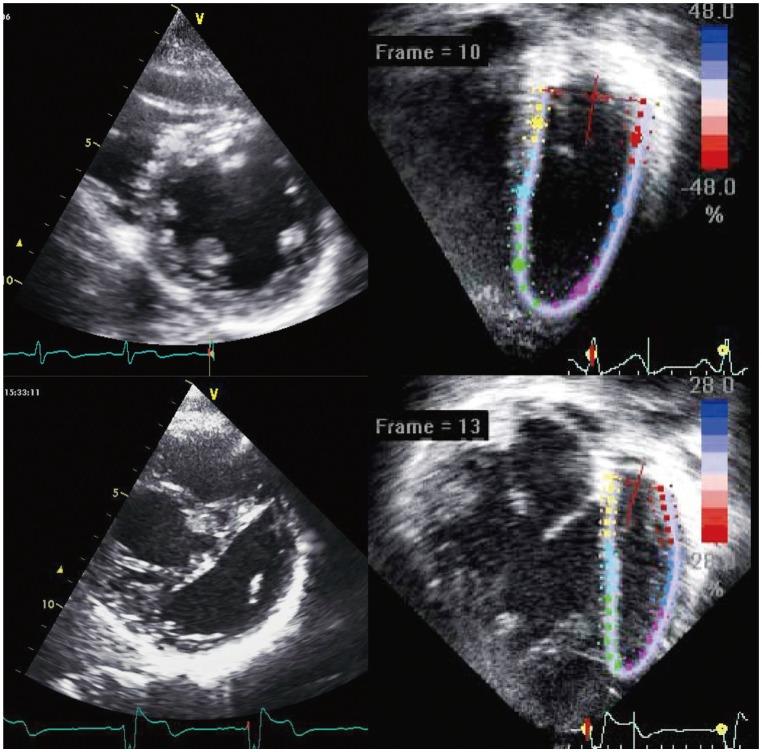

Significant improvement in survival of children with congenital cardiac malformations has resulted in an increasing population of adolescent and adult patients with congenital heart disease. Of the long-term cardiac problems, ventricular dysfunction remains an important issue of concern. Despite corrective or palliative repair of congenital heart lesions, the right ventricle, which may be the subpulmonary or systemic ventricular chamber, and the functional single ventricle are particularly vulnerable to functional impairment. Regular assessment of cardiac function constitutes an important aspect in the long-term follow up of patients with congenital heart disease. Echocardiography remains the most useful imaging modality for longitudinal monitoring of cardiac function. Conventional echocardiographic assessment has focused primarily on quantification of changes in ventricular size and blood flow velocities during the cardiac cycles. Advances in echocardiographic technologies including tissue Doppler imaging and speckle tracking echocardiography have enabled direct interrogation of myocardial deformation. In this review, the issues of ventricular dysfunction in congenital heart disease, conventional echocardiographic and novel myocardial deformation imaging techniques, and clinical applications of these techniques in the functional assessment of congenital heart disease are discussed.

先天性心脏畸形患儿生存率的显著提高,使得先天性心脏病的青少年和成年患者群体不断增加。在长期的心脏问题中,心室功能障碍仍然是一个重要的关注点。尽管对先天性心脏病变进行了矫正或姑息性修复,但右心室(可能是肺下或体循环心室腔)以及功能性单心室特别容易受到功能损害。定期评估心脏功能是先天性心脏病患者长期随访的一个重要方面。超声心动图仍然是纵向监测心脏功能最有用的成像方式。传统的超声心动图评估主要集中在量化心动周期中心室大小和血流速度的变化。包括组织多普勒成像和斑点追踪超声心动图在内的超声心动图技术的进步,使得能够直接检测心肌变形。在这篇综述中,讨论了先天性心脏病中的心功能障碍问题、传统超声心动图和新型心肌变形成像技术,以及这些技术在先天性心脏病功能评估中的临床应用。